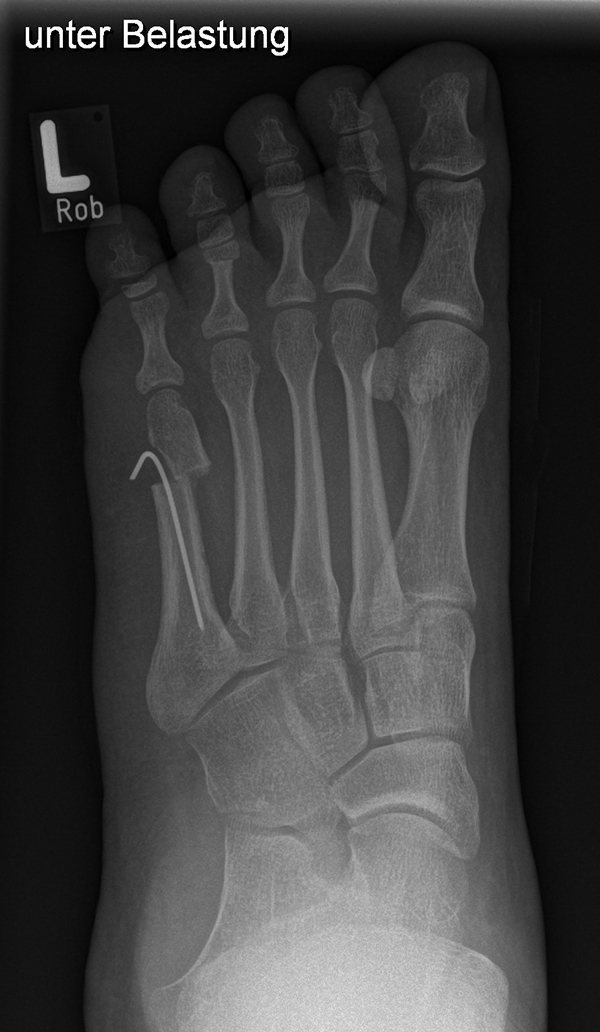

Die Chevron Osteotomie 1 ist ohne Komplikationen am wachsenden Skelett durchführbar. Das Metatarsale I besitzt distal keine Wachstumsfuge, die geschädigt werden könnte. Die „französische Methode nach Marc Elkaim“ eignet sich für Kinder ganz besonders (Abb. 28).

Abb. 28 a-g: Radiologischer Verlauf einer Chevronosteotomie nach dem Verfahren von M. Elkaim mit prä- (a-c drei unterschiedliche Ansichten) und intraoperativen Röntgenbildern in zwei Ansichten (d-e) sowie postoperativ zwei Ansichten (f-g).

Zum Lesen der Bildbeschreibung und zur Vollansicht bitte die Bilder anklicken. Bilder: A. Helmers.

Sie wird über eine eigene Tapetechnik fixiert und kann bei einem erhöhten Intermetatarsale-Winkel alternativ zur Scarf-Osteotomie durchgeführt werden. Nachteile der Methode sind eine deutliche Verkürzung durch die Fräse sowie eine starke Plantarisierung des Metatarsale I Köpfchens. Um die Verkürzung zu vermeiden, wird verlängernd in Richtung des Metatarsale II Köpfchens (nicht wie offen in Richtung Metatarsale IV Köpfchen) osteotomiert. Gleiches gilt für die starke Plantarisierung, die durch den Knochenverlust der Fräse entsteht. Die Korrektur eines kindlichen oder jugendlichen Hallux valgus ist mit der Methode ansonsten suffizient durchführbar. Wird verkürzt, muss ausreichend plantarisiert werden, um eine Transfer-Destabilisierung MT II-IV zu vermeiden.

Die MICA-Technik sollte bei geschlossenen Fugen mit einem weitem intermetatarsale Winkel durchgeführt werden. Die dafür typische Verschraubung der Osteotomie kann bei geschlossenen Fugen ohne Probleme erfolgen. Diese Osteotomie kann gut mit einer Akin- und den beschriebenen Kleinzehen-Osteotomien kombiniert werden.